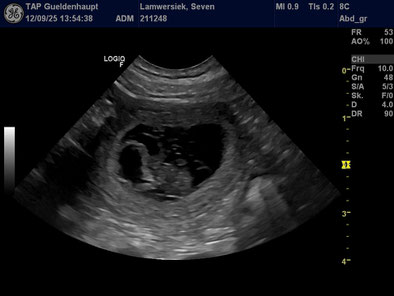

12.09.2025

Heute waren wir beim Tierarzt zum Ultraschall und konnten sehen, dass uns unser Gefühl nicht getäuscht hat. Seven bekommt Welpen. Wir erwarten unseren R-Wurf Mitte Oktober.